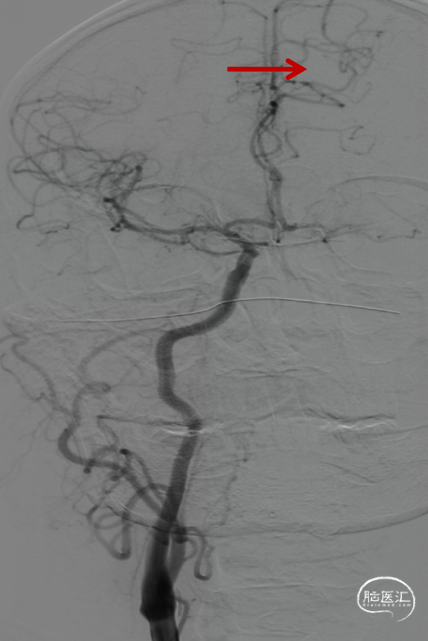

术前造影提示左侧颈内动脉自起始部闭塞,前交通动脉开放,同侧大脑前动脉及大脑后动脉皮层对左侧半球形成皮层侧支代偿。

微导管微导丝携SKATHI远端通路导管负压状态下再次进入颈内动脉,造影确认颈内动脉通畅,大脑中动脉中远段可见栓塞。

微导管越过大脑中动脉血栓后,以4-20mm Solitaire AB支架,配合6F 115cm SKATHI远端通路导管取栓一次,复查造影大脑中动脉血栓通畅,远端仍有少许血栓,观察后血流能够维持。